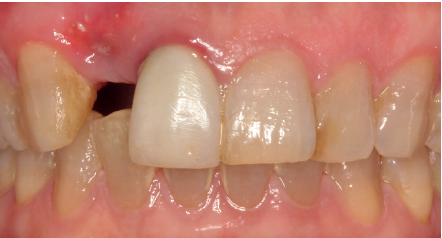

Se presenta el caso de una mujer de 36 años que acude a la consulta demandando solución para un implante situado en la posición 1.2. Este implante ha llevado una rehabilitación con una corona durante un corto período de tiempo en el que se produjo una mucositis importante y una pérdida del grosor del tejido gingival, por lo que la corona fue retirada.

La paciente presenta un provisional removible y el tejido blando circundante a la zona de la emergencia inicial de la prótesis implantosoportada se encuentra en malas condiciones, con una pérdida de grosor importante y los restos de una fístula de tejido blando (Figuras 1-4).